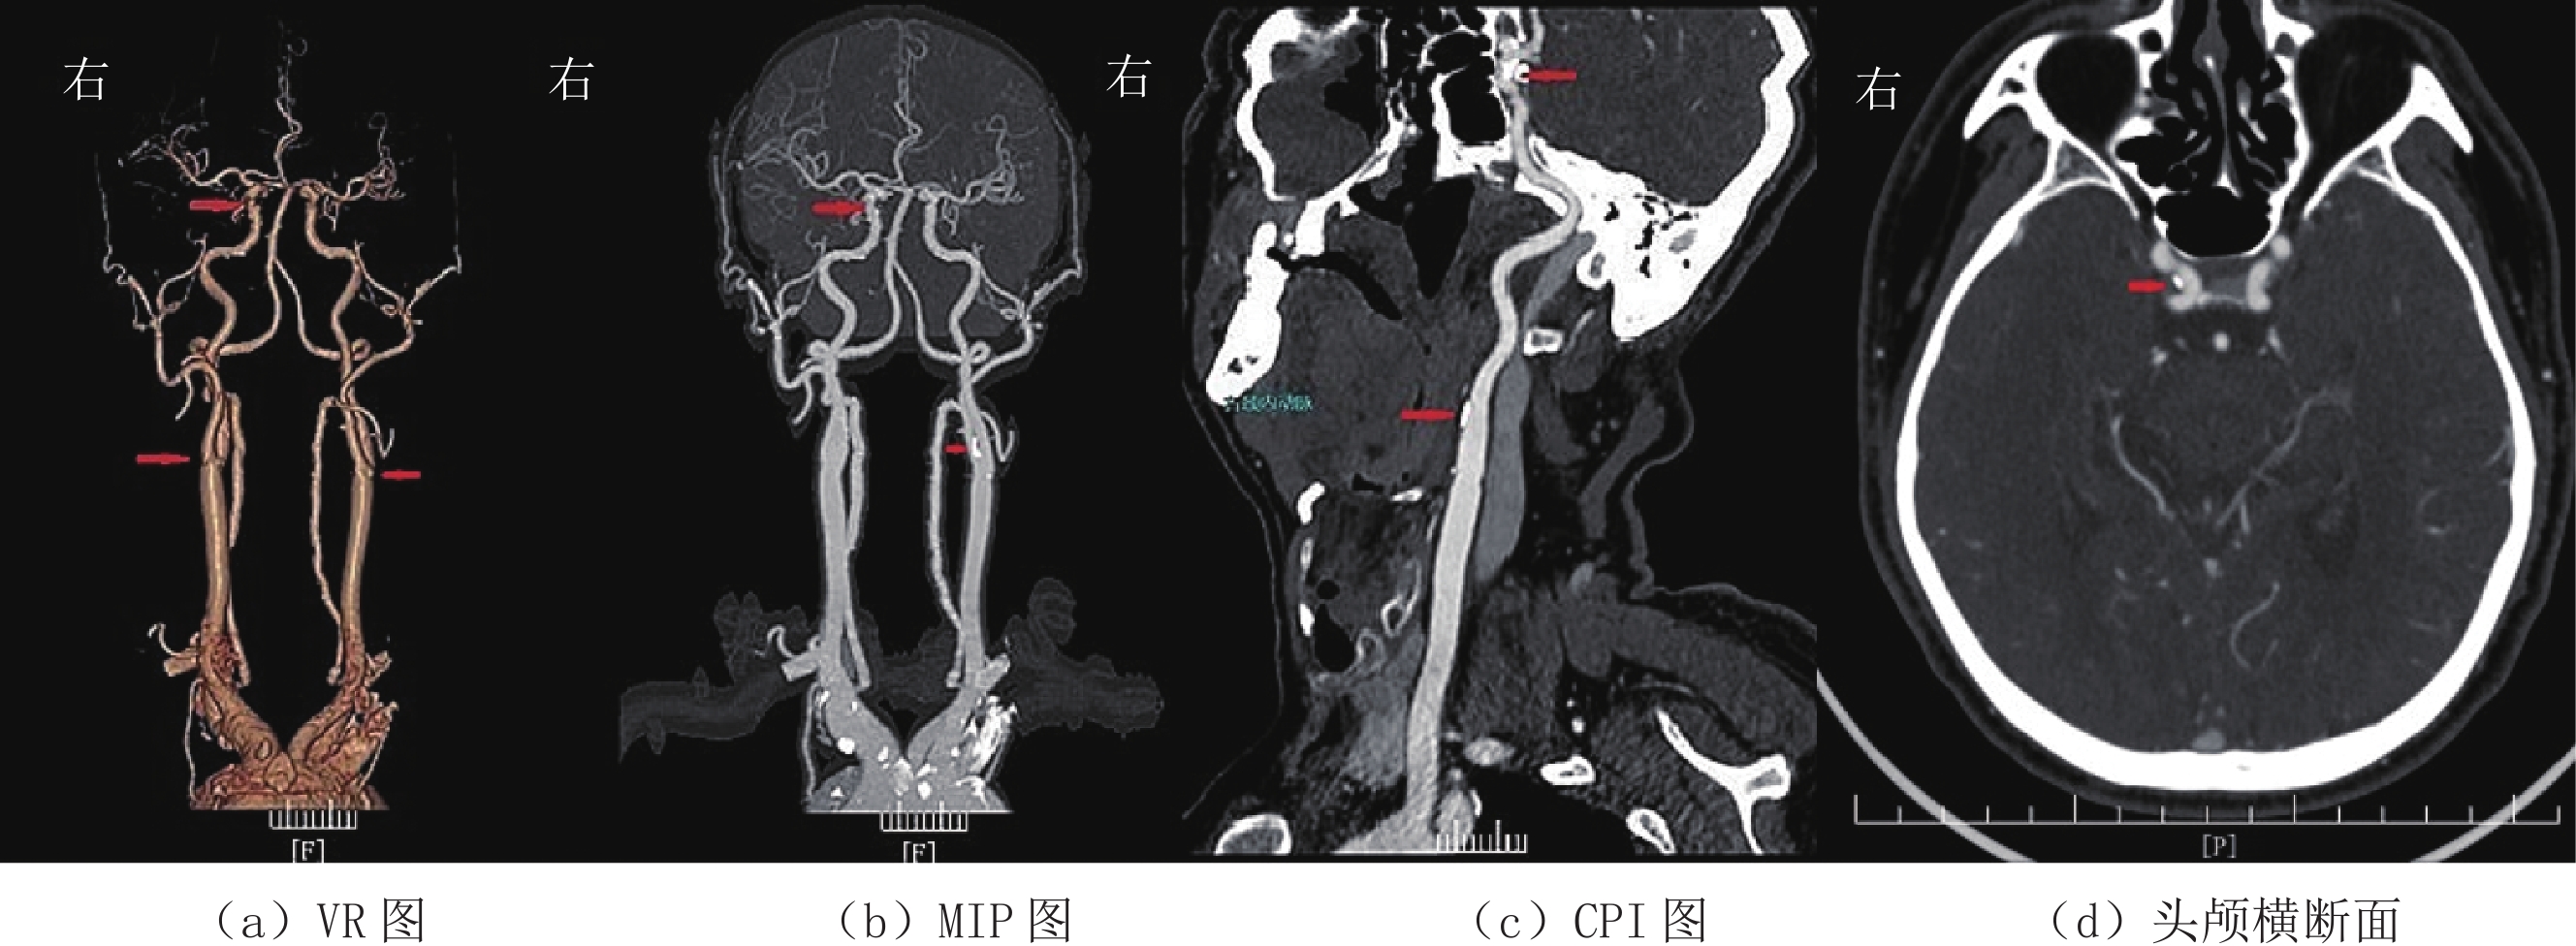

1.4.2 图像主观评分

采用双盲法由两位高年资主治医师对3组患者的横断面图像、VR、MIP以及CPI图像质量进行评分(图1~图3)。评分标准采用5分法[6],5分:图像质量好,血管与组织对比鲜明,细微解剖结构清晰,噪声小;4分:图像质量较好,血管与组织对比较好,解剖结构较清晰,噪声较小;3分:图像质量一般,血管解剖结构显示一般,噪声略大;2分:图像质量较差,血管解剖结构不清,噪声较重;1分:图像质量差,血管解剖结构不清,噪声极为严重。评分大于或等于3分视为满足诊断要求。

(1)众所周知,X线经过人体时会产生康普顿效应和光电效应;X线光子能量会随着管电压的下降而下降,当X线光子能量接近碘原子的K临界值(33 keV)时衰减值最大,这样导致所测得的CT值会随着管电压的下降而增高[13-15]。本研究结果显示:管电压从120 kV降到100 kV、80 kV时,大脑中动脉M1段血管的CT值分别为(334.21±69.42)HU、(385.00±85.53)HU、(502.50±110.17)HU,与学者的研究基本一致[10,16-18]。由于含碘血管腔的CT值是头颈部CTA图像质量的关键所在,也是观察血管病变和VR、MIP及CPI成像的基础。研究发现[16-18]血管腔内的CT值以350~550 HU时最佳,过低或过高都不利于血管细节的显示,会影响粥样斑块的显示和血管狭窄程度的判断。本研究大脑中动脉M1段血管CT值在管电压等于100 kV时最接近这个数值。同时,从本研究3组图像质量主观评分也可以看出管电压为100 kV时评分最高。两组数据都可以证明,管电压在100 kV时,图像质量最好。

(2)图像噪声是评价图像质量另外一个很关键的因素[10,19]。管电压一旦下降,X线的质量和穿透力都会随之下降。特别是颅内段血管,由于高致密颅骨的遮挡,X线光子到达探测器的数量便会减少,SD值增大,图像颗粒感明显增大,影响对病变细节的观察。本研究显示,管电压降至80 kV时,主动脉弓和大脑中动脉M1段的SD值明显上升,上升幅度为60% 和86%,并不利于病变细节的观察。